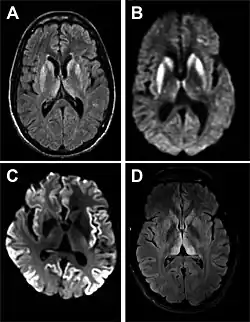

MRI of iCJD because of growth hormone

The defective protein can be transmitted by contaminated harvested human brain products, corneal grafts,[28] dural grafts,[29] or electrode[30] implants and pituitary human growth hormone, which has been replaced by recombinant human growth hormone that poses no such risk.[31]

• MRI with diffusion weighted inversion (DWI) and fluid-attenuated inversion recovery (FLAIR) shows a high signal intensity in certain parts of the cortex (a cortical ribboning appearance), the basal ganglia, and the thalami.[42] The most common presenting patterns are simultaneous involvement of the cortex and striatum (60% of cases), cortical involvement without the striatum (30%), thalamus (21%), cerebellum (8%) and striatum without cortical involvement (7%). In populations with a rapidly progressive dementia (early in the disease process), MRI has a sensitivity of 91% and specificity of 97% for diagnosing CJD.[46] The MRI changes characteristic of CJD may also be seen in the immediate aftermath (hours after the event) of autoimmune encephalitis or focal seizures.[42]

Imaging of the brain may be performed during medical evaluation, both to rule out other causes and to obtain supportive evidence for diagnosis. Imaging findings are variable in their appearance and also variable in sensitivity and specificity.[49] While imaging plays a lesser role in diagnosis of CJD,[50] characteristic findings on brain MRI in some cases may precede onset of clinical manifestations.[51]

Brain MRI is the most useful imaging modality for changes related to CJD. Of the MRI sequences, diffuse-weighted imaging sequences are most sensitive.[52] Characteristic findings are as follows:

dwMRI, FDG PET and post mortem histology from a patient who presented with sCJD aged 66

• Focal or diffuse diffusion-restriction involving the cerebral cortex or basal ganglia. The most characteristic and striking cortical abnormality has been called "cortical ribboning" or "cortical ribbon sign" due to hyperintensities resembling ribbons appearing in the cortex on MRI.[53] The involvement of the thalamus can be found in sCJD, is even stronger and constant in vCJD.[54]

• Varying degree of symmetric T2 hyperintense signal changes in the basal ganglia (i.e., caudate and putamen), and to a lesser extent globus pallidus and occipital cortex.[50]

Brain FDG PET-CT tends to be markedly abnormal, and is increasingly used in the investigation of dementias.

• Patients with CJD will normally have hypometabolism on FDG PET.[55]